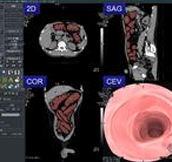

CT Colonoscopy with automatic colon area extraction from abdominal CT image. Display switchable to ?cruising?, ?3 section? and ? panorama mode.

Color and display to process possible. Shape analysis filter (colored polyp on panoramic image)